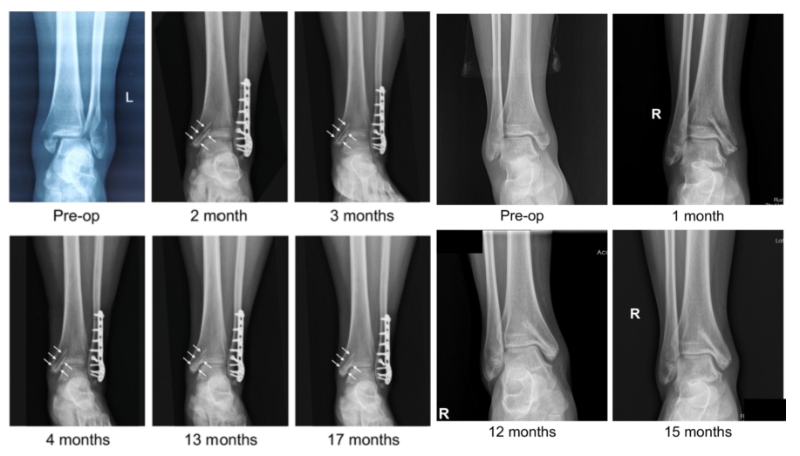

近日,國(guó)際骨科臨床轉(zhuǎn)化期刊《Journal of Orthopaedic Translation》在線發(fā)表了由上海交大戴尅戎院士、郝永強(qiáng)教授團(tuán)隊(duì)和丁文江院士、袁廣銀教授團(tuán)隊(duì)合作發(fā)表的可降解鎂合金骨釘1-2年的臨床試驗(yàn)觀察結(jié)果,所有患者術(shù)后內(nèi)踝骨折愈合,功能恢復(fù)。研究證實(shí)了可降解鎂合金螺釘治療內(nèi)踝骨折的臨床療效及其生物安全性,為全降解鎂合金植入物等高端醫(yī)療器械進(jìn)一步的臨床推廣應(yīng)用奠定了堅(jiān)實(shí)基礎(chǔ),相關(guān)成果以“Effectiveness and safety of biodegradable Mg-Nd-Zn-Zr alloy screws for the treatment of medial malleolar fractures”為題在線發(fā)表于Journal of Orthopaedic Translation,27 (2021) 96–100。這是國(guó)內(nèi)首個(gè)可降解醫(yī)用鎂合金臨床試驗(yàn)的公開(kāi)報(bào)道,也是國(guó)際首款含有功能涂層的可降解鎂合金骨釘?shù)呐R床試驗(yàn)結(jié)果的公開(kāi)報(bào)道,具有里程碑意義。

醫(yī)用鎂合金骨內(nèi)植物臨床試驗(yàn)研究突破性進(jìn)展(圖1)